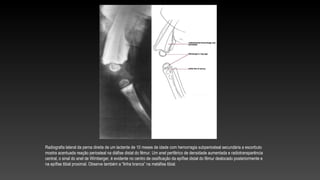

Rx perfil da porção distal do fêmur de uma mulher de 28 anos de idade mostra infarto medular extenso e

neo-osteogênese periosteal, produzindo uma aparência em “osso dentro de osso”.